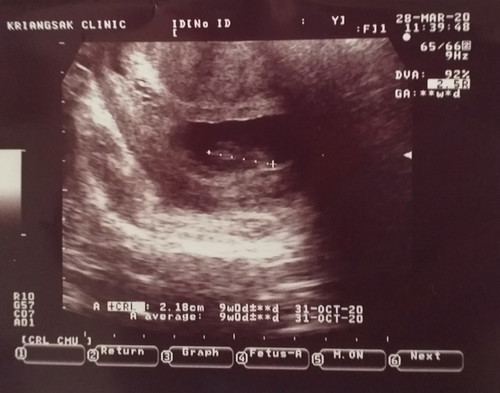

อายุครรภ์นับจากประจำเดือนวันเเรกของเดือนสุดท้ายคือท้อง10+2

เราพึ่งไปอัลตร้าซาวมาได้9w หมายความว่าไข่ตกช้าใช่มั้ยค่ะ หรือว่าเราแพ้ท้องจนกินอะไรไม่ได้แล้วลูกตัวเล็ก